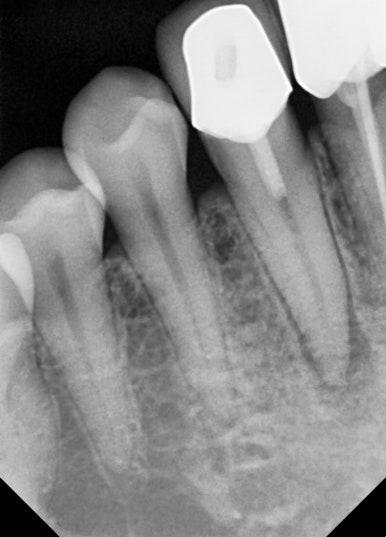

📸 케이스 4: #43 Re-Endo

- 잇몸에 여드름처럼 볼록한 염증이 올라옴

- 치근단 염증 및 헐거운 충전 확인

- 재신경치료로 염증 완치

✅ 육안으로 보이던 염증도 완전 치유